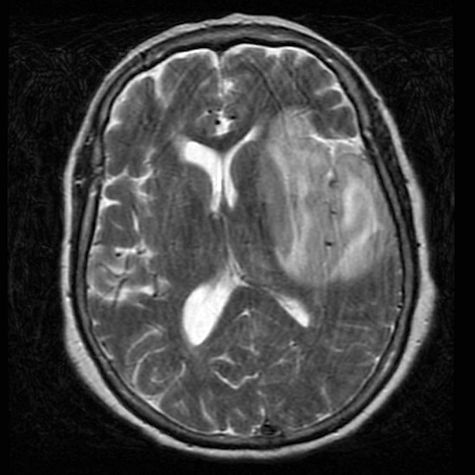

En el caso del paciente que se presenta, la RM no mostró los cambio típicos en el tallo encefálico (Ver Fig Nº 3), pero había unas zonas hiperintensas en T2 hacia los nucleos de la base y parte del tálamo, que podían estar relacionadas con una Mielinolisis osmótica, aunque se sugirió que igualmente podría tratarse de un Herpes cerebral. Desafortunadamente no se realizó una nueva punción lumbar para estudio de herpes virus y, al fallecimiento del paciente, no se realizó autopsia que hubiera permitido toma muestra de tejido cerebral. La RMN puede orientar el diagnóstico, pero de ninguna manera es confirmatoria ni puede separar con seguridad los dos procesos.

Fig Nº 3. RMN del paciente descrito, que muestra áreas hiperintensas en el FLAIR en los núcleos de la base y parte del tálamo, que pueden estar asociadas a mielinolis osmótica.